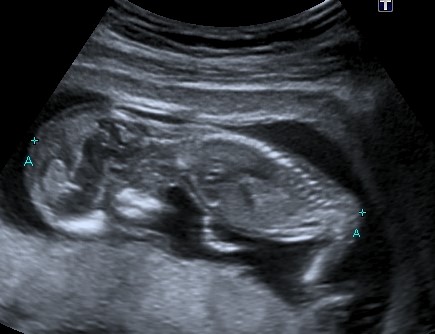

No good nub shots though. This is bubs skull, potty shot (though baby was 12&1 at my scan but measuring ahead at 13wks, so I think its way too early) and a side profile. Would love some educated guesses.